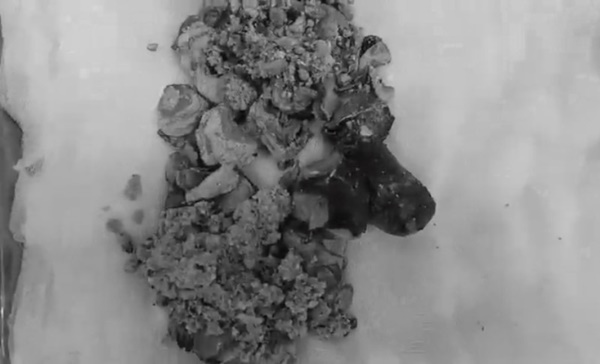

Sỏi khổng lồ nặng 500g đã được các bác sĩ bóc tách. Ảnh BSCC.

Bác sĩ đã quyết định mổ mở để lấy sỏi thận. Quá trình phẫu thuật, các bác sĩ bóc tách được viên sỏi san hô dài tới 20cm, nặng 500g. Bác sĩ Liên cho biết trường hợp này may mắn vì chức năng thận đã phục hồi, bệnh nhân không phải chạy thận chu kỳ. Sau 10 ngày điều trị theo dõi, sức khỏe bệnh nhân đã hồi phục và ra viện.